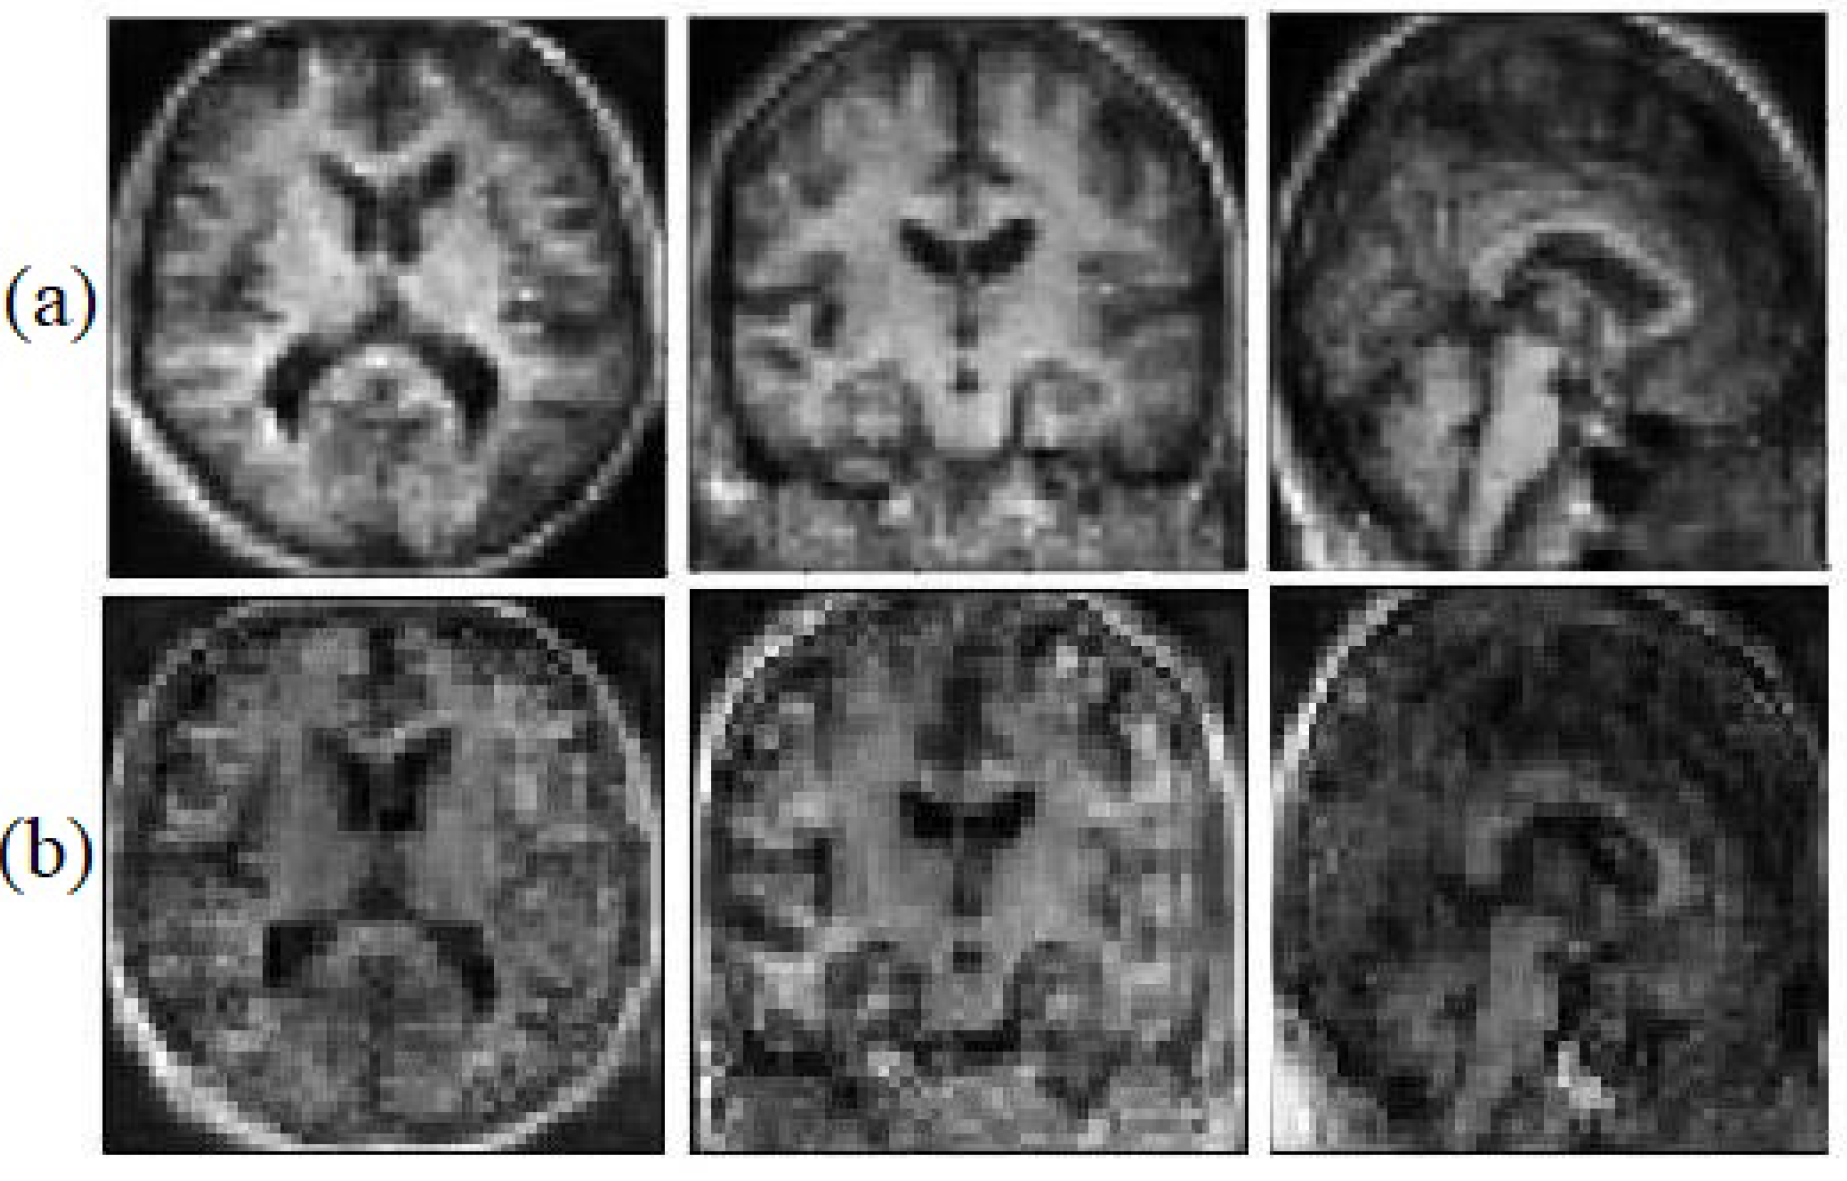

We believe that the geometrical and edges information can help the model to face the saturation problem less. This information helps the generator to be able to catch up with the discriminator faster. Figure 6, illustrates the synthetic images with geometrical information and without geometrical information.

Figure 6.

Synthetic MRI with the Sobel filter (a) and without the Sobel filter (b).

5.2. Structural Analysis

Visual analysis is one of the most common ways to evaluate generated images. To ensure that the structural information is not missed, the generated images have been evaluated after segmenting the generated image as well. We segmented each image into three classes (white matter, grey matter, and CSF) to examine if the model has generated miss-placed voxels. Figure 7, illustrates the ground truth segmented T1 weighted MRI and the synthetic image after the segmentation.

Figure 7.

The ground truth (a) and the synthetic T1 weighted MRI (b).

The proposed model almost predicts the structure of the grey matter correctly so the generated grey matter can be used in order to correct the partial volume effect, on PET images. We have replicated the analysis with 10 subjects and measured the average voxel values between the ground truth and the generated images for each tissue. Figure 8, represents the average of voxel values.